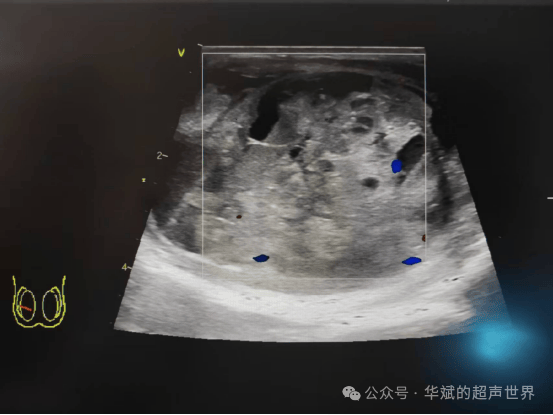

嗯嗯嗯问: 年轻患者,主诉左侧阴囊,无压痛,无发热。临床疑诊睾丸炎。超声检查发现:右侧睾丸肿大,约7.1×3.8×4.1cm,内部强弱回声不均,可见弥漫分布的大小不等的无回声。睾丸内可见点状血流信号。